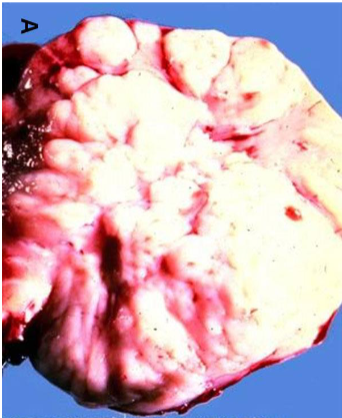

Oncocytoma

dense pink cytoplasm (eosinophilic) cell nests with bland nuclei; little mitotic activity in a paucicellular hyalinized stroma

Benign

Gross: well circumscribed but unencapsulated, brown to yellow, often with central scar

Micro: dense pink cytoplasm (eosinophilic) cell nests with bland nuclei; little mitotic activity in a paucicellular hyalinized stroma